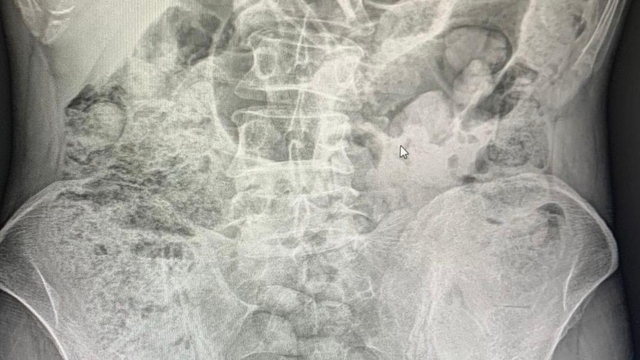

Siirt Emniyet Müdürlüğü Narkotik Suçlarla Mücadele Şube Müdürlüğü görevlilerince 14 Aralıkta Baykan Şehit Bünyamin Torgut Polis Uygulama Noktasında durdurulan iki araçta, batı illerine uyuşturucu madde sevk etmek için uyuşturucu maddeleri özel yöntemler kullanarak paketleyerek yutmak yöntemiyle mide kısmında taşıyan İran uyruklu 3 kadın 1 erkek şahıs yakalanmıştı. Şahısların midelerinde bulunan uyuşturucu maddeler 10 gün devam eden hastane süreci sonucunda cerrahi yöntemler kullanılarak çıkartıldı.

Şüpheli şahısların midelerinden 119 paket halinde 1 kilo 597 gram uyuşturucu madde çıkartıldı. Zanlılar, sevk edildikleri adli makamlarca tutuklanarak cezaevine sevk edildi.